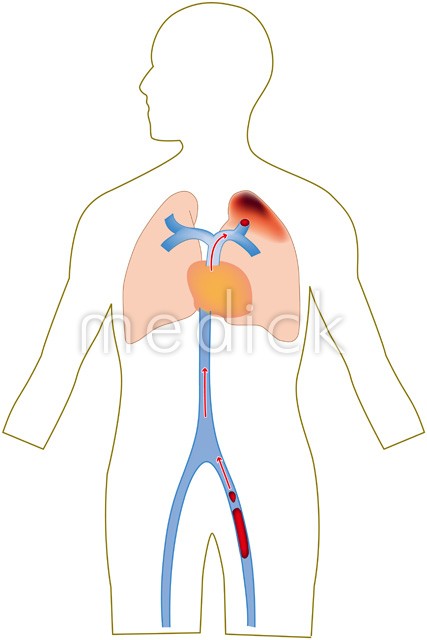

エコノミークラス症候群のイラスト素材29373435- PIXTA。

川崎 静脈血栓塞栓症浅田内科・循環器内エコノミークラス症候群。

エコノミークラス症候群広島の調剤薬局 FINE PLUS まえだ薬局・プラス薬局 のブログ。

4 エコノミークラス症候群 肺血栓塞栓症 に関するQ&A - 4 エコノミークラス症候群 肺血栓塞栓症 に関するQ&A -災害時の対応について一般社団法人日本呼吸器学会。

解剖生理学攻略ページ - この四コマ漫画を見ると ・エコノミー症候群 ・深部静脈血栓症 ・肺塞栓症Facebook。

肺血栓症のイラスト - 医療のイラスト・写真・動画、素材販売サイトのメディック medick。

エコノミークラス症候群病気と治療の検索サイト「メディカルブレイン」。

川崎 静脈血栓塞栓症浅田内科・循環器内エコノミークラス症候群。

肺血栓塞栓症・エコノミークラス症候群 男性 のイラスト – フリーイラスト素材集 KuKuKeKe。

肺血栓塞栓症のベクター画像イラスト。血管血栓症」のベクター画像素材 ロイヤリティフリー737751463Shutterstock。

エコノミークラス症候群震災時に起こりやすい健康問題と予防法 1看護roo! カンゴルー。

4 エコノミークラス症候群 肺血栓塞栓症 に関するQ&A - 4 エコノミークラス症候群 肺血栓塞栓症 に関するQ&A -災害時の対応について一般社団法人日本呼吸器学会。

4 エコノミークラス症候群 肺血栓塞栓症 に関するQ&A - 4 エコノミークラス症候群 肺血栓塞栓症 に関するQ&A -災害時の対応について一般社団法人日本呼吸器学会。

慢性血栓塞栓性肺高血圧症千葉大学大学院医学研究院 呼吸器内科学。

エコノミークラス症候群 深部静脈血栓症 メカニズムのイラスト素材29374549- PIXTA。

エコノミークラス症候群:入院中に死亡8件 医療事故調査毎日新聞。